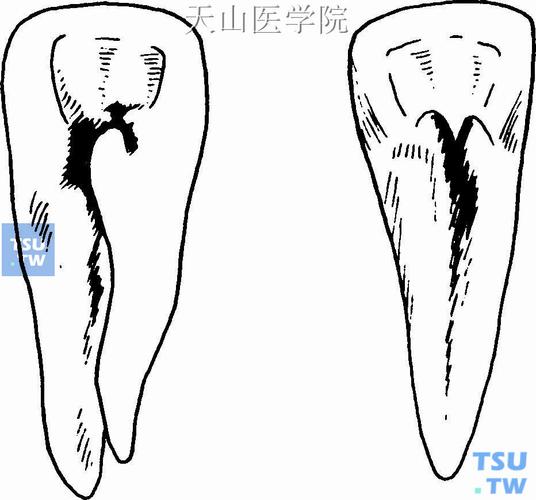

在牙舌侧颈部有个隆起—舌隆突(黑色)

畸形舌侧窝x线表现:舌隆突特别突起,在舌面可见致密高起的小牙尖.